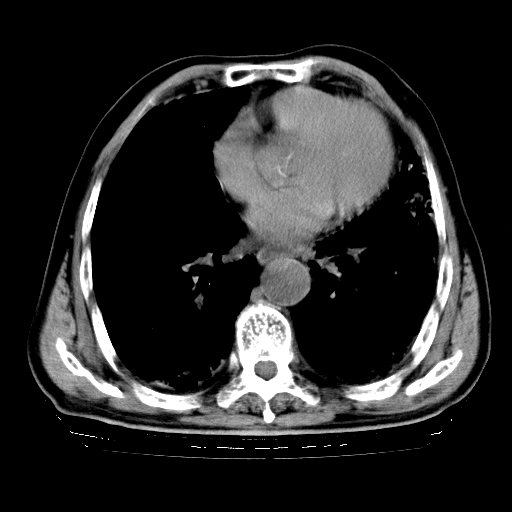

标题: CT25149:男,69岁,反复咳嗽、咳痰五年余,呼吸困难三天。 [打印本页]

男,69岁,反复咳嗽、咳痰五年余,呼吸困难三天。

慢支伴感染、肺气肿、肺心病

慢支伴感染、肺气肿、肺心病!支持!另:间质纤维化!

两肺间质性炎症并感染,左上叶肉芽肿

考虑慢性间质性肺炎并肺间质纤维化。

慢支伴感染、肺气肿、肺心病。双肺间质性改变(间质纤维化)。